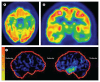

Brain imaging has a crucial role in the presurgical assessment of patients with epilepsy. Structural imaging reveals most cerebral lesions underlying focal epilepsy. Advances in MRI acquisitions including diffusion-weighted imaging, post-acquisition image processing techniques, and quantification of imaging data are increasing the accuracy of lesion detection. Functional MRI can be used to identify areas of the cortex that are essential for language, motor function, and memory, and tractography can reveal white matter tracts that are vital for these functions, thus reducing the risk of epilepsy surgery causing new morbidities. PET, SPECT, simultaneous EEG and functional MRI, and electrical and magnetic source imaging can be used to infer the localisation of epileptic foci and assist in the design of intracranial EEG recording strategies. Progress in semi-automated methods to register imaging data into a common space is enabling the creation of multimodal three-dimensional patient-specific datasets. These techniques show promise for the demonstration of the complex relations between normal and abnormal structural and functional data and could be used to direct precise intracranial navigation and surgery for individual patients.